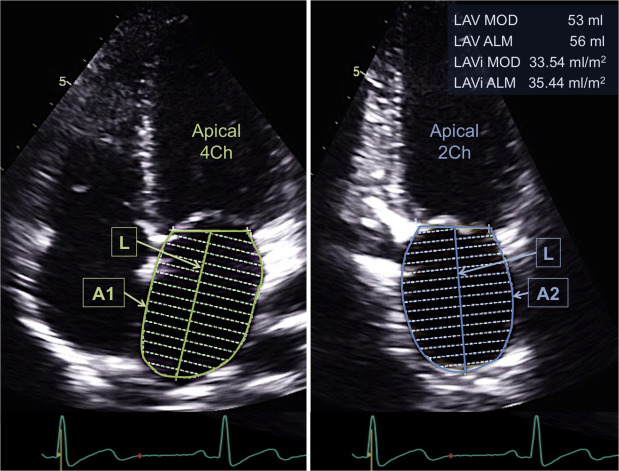

(3) LAVI (LA volume index) : 사실 LAVI는 이완기장애가 급성인지, 만성인지를 평가하는 기준이다.

LAVI가 크면 이완기장애가 chronic, LAVI가 작으면 acute임을 시사한다.

눈대중으로 봤을 때, LA가 LV의 절반이면 정상, 그보다 크면 비정상적으로 커져 있는 상황.

| Normal | Mild | Moderate | Severe | |

| LAVI | ≤ 28 ㎖/㎡ | 29~33 ㎖/㎡ | 34~39 ㎖/㎡ | ≥ 40 ㎖/㎡ |